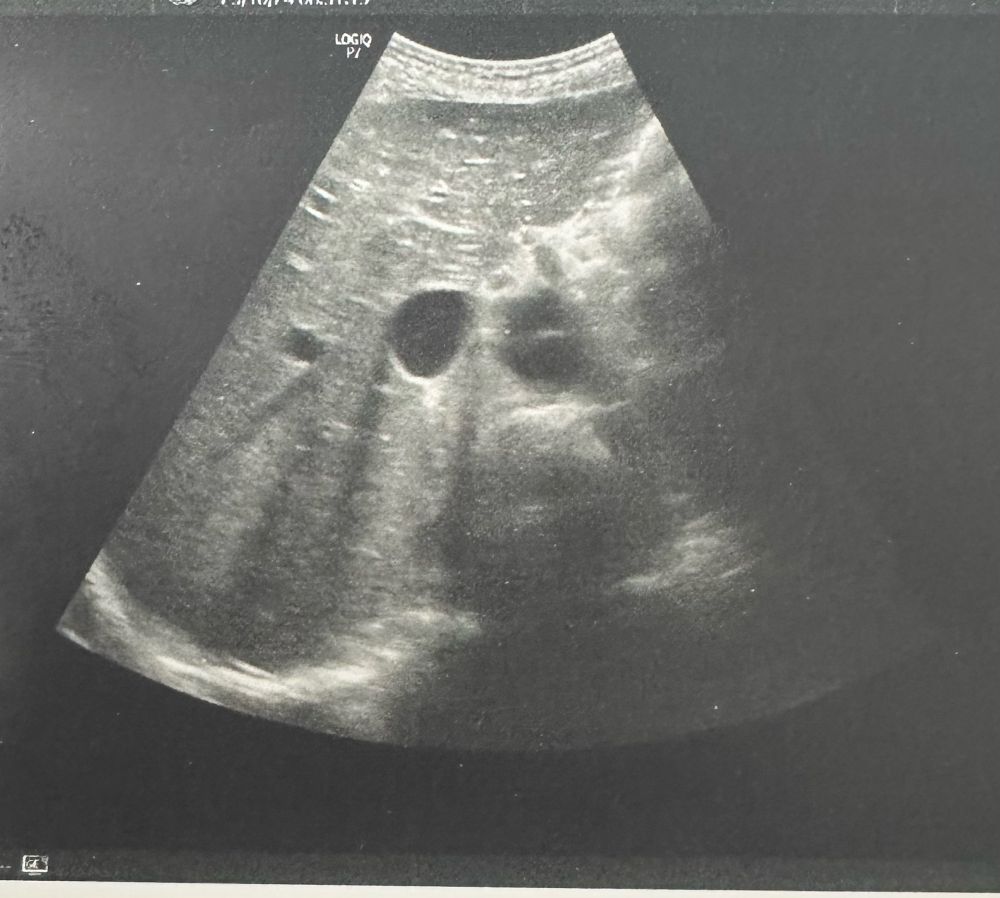

Hier noch ein Sagitaltschnitt auf gleicher Höhe. Die Aortendissektion ist bewiesen. Das CT ist schon bereit, wir hatten beim klinischen Bild darauf getippt und den Tisch so schnell wie möglich frei gewünscht. Die Kollegen von der Gefäßchirurgie rufe ich derweil mal an…

Da die Vitalparameter ja stabil sind und die Patientin schmerzen hat, bekommt sie 0,2mg Fentanyl. Weiterhin etablieren wir zeitgleich einen 2. Zugang(grün) am rechten Arm(links hat der NA bereits grün verbaut) . Ich schnappe mir derweil den Schallkopf. Bitte Alt beachten!

Bauch und linken Bein auf. Weiterhin median Lap Narbe bei Z.n. HE vor vielen Jahren.

Das CT ist gemacht. Die Dissektion beginnt 1mm nach Abgang der Subclavia rechts. Die linke Niere ist nicht mehr versorgt - die erklärt den Rückenschmerz der Patientin. Ebenfalls ist die iliaca links nicht mehr versorgt was den Beinschmerz und in die Lähmung erklärt.